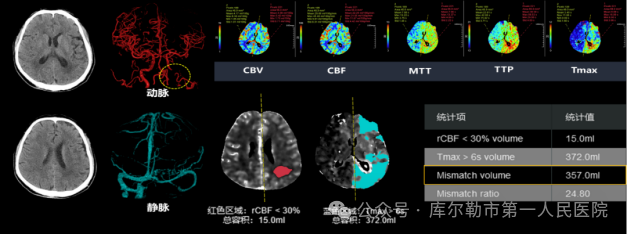

2、一站式卒中检查-立体直观全脑覆盖

超高端320排CT可实现单圈扫描的全脑覆盖成像,一次检查即可获得全脑平扫图像、动静脉造影图像和灌注图像,以及缺血半暗带和核心梗死区的分析,不仅可应用于急诊缺血性脑卒中的影像评估,还可助力脑血管畸形、脑动脉瘤等其他脑血管病的结构和功能评估,同时配以低剂量平台,保证患者在低剂量水平完成卒中扫描。